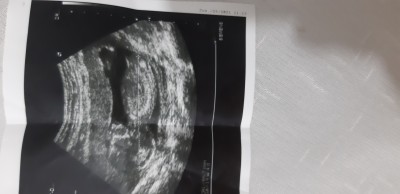

nup teorisinden anlayanlar cinsiyet ne bakabilirmisiniz tsk ederim simdiden

Gebelik haftası 14.4